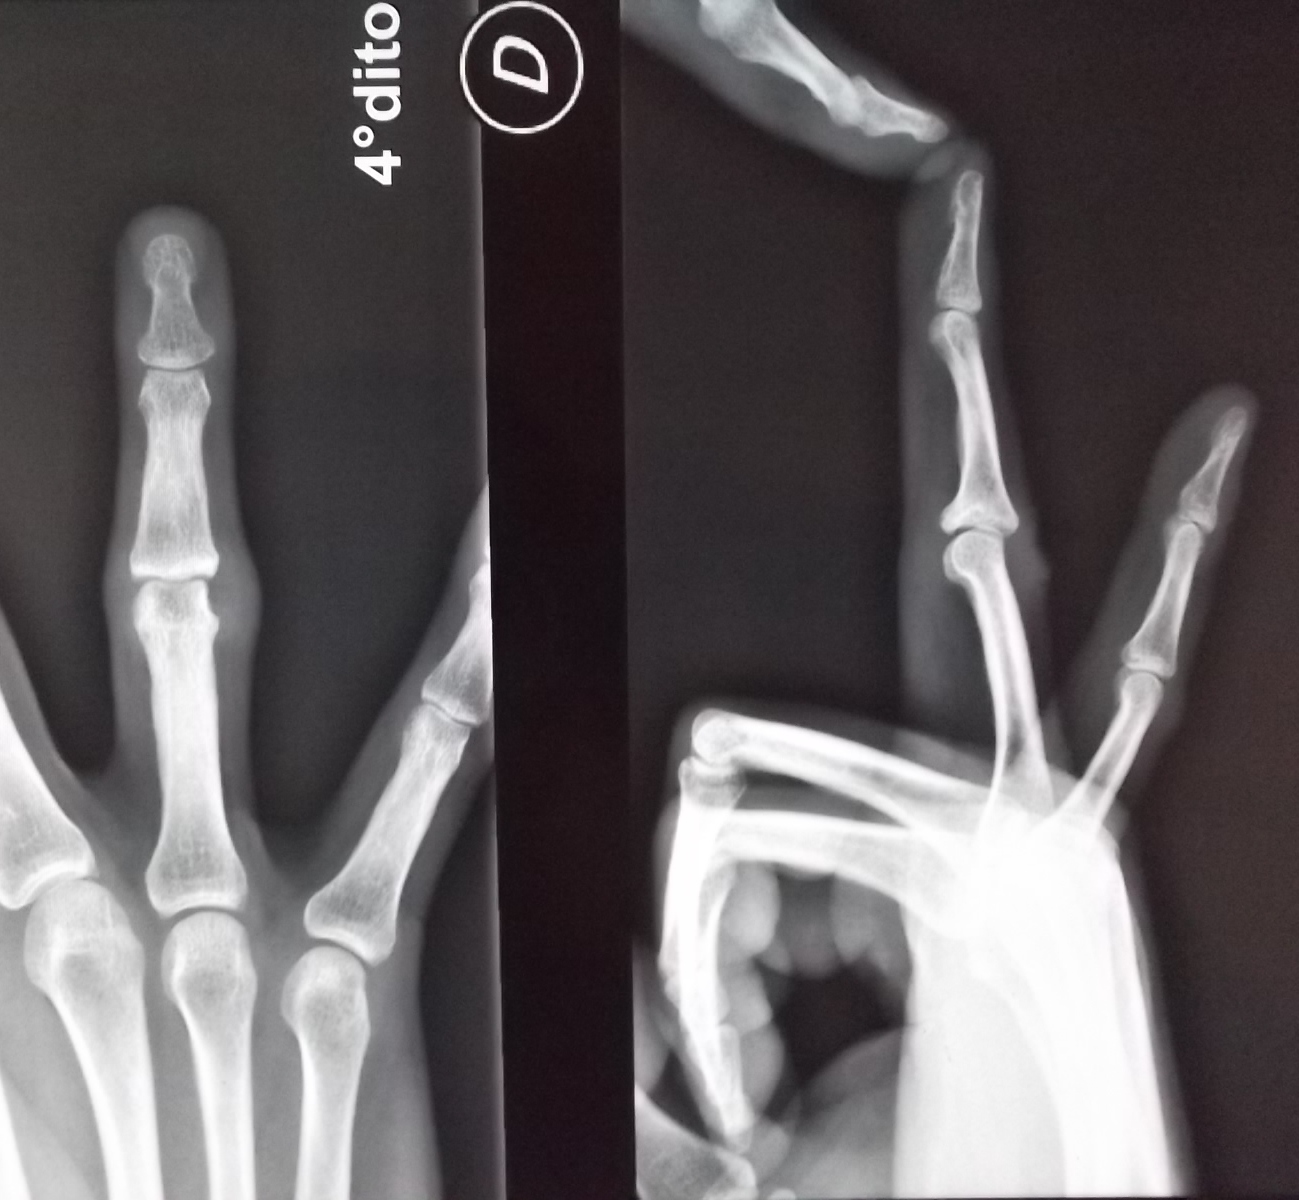

Buongiorno nel 2010 a seguito di compressione e stiramento di una fune attorno alla mia mano (tiravo una fune insieme ad altre persone in fila e l'ho avvolta intorno alla mano per fare maggiore presa ma purtroppo le persone dietro di me hanno bruscamente tirato la fune che mi ha stretto violentemente la mano) ho avuto una frattura alla base della falange intermedia del 4° dito della mano destra. Ho messo la stecca e dopo averla tolta ad oggi in corrispondenza della frattura ho un ispessimento del dito o gonfiore rigido. Convinta che l'osso non fosse stato riposizionato nella sua posizione corretta ho rieseguito una RX ed è tutto ok. Riesco a muovere interamente il dito. Di cosa di tratta questo ispessimento poco estetico non trattandosi di osso? Come posso risolverlo per ridurlo ed attenuarlo? Che accertamenti fare?

Commento file: Dopo la stecca ovvero adesso

DOPO.jpg

Commento file: Prima della stecca

PRIMA1.jpg

DITO2.jpg

Dal 2010 sono passati 6 anni !??!! Certo mi mandi foto del dito e della radiografia . A presto